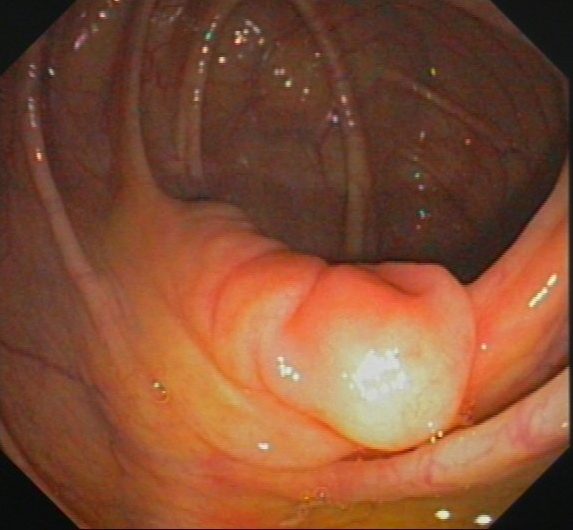

Wenn bei der Darmspiegelung Polypen gefunden werden, können diese in aller Regel während des Eingriffs entfernt werden (Polypektomie). Es handelt sich meist um Adenome, von Drüsengewebe des Dickdarms ausgehende Tumoren. Aus diesen - eigentlich gutartigen - Läsionen können sich innerhalb von Jahren bösartige Tumoren (Dickdarmkrebs) entwickeln. Die Vorsorgekoloskopie und Polypektomie können effektiv Darmkrebs verhindern.

Zur Abtragung gestielter Polypen wird eine Drahtschlinge über das Endoskop eingeführt und um den Stiel gelegt. Dann wird diese zugezogen und der Polyp wird mit hochfrequentem Strom abgeschnitten. Durch die Hitze, die dabei entsteht, werden Gefäße verschlossen, so dass meist keine relevante Blutung auftritt.

Viele Polypen sind flach und damit mit der Schlinge nicht so gut zu fassen. Bei solchen Polypen ist eine Chromoendoskopie mit Indigokarmin hilfreich, um sie besser abgrenzen zu können. Dann wird mit einer Injektionsnadel, die auch durch das Endoskop eingeführt wird etwas verdünnte Adrenalinlösung in die Schleimhaut unter dem Polypen injiziert. Der Polyp hebt sich halbkugelig ab und kann mit der Schlinge gefasst und abgeschnitten werden. Durch das Adrenalin verengen sich die Gefäße des Polypen, so dass eine Blutung verhindert wird.

Kommt es dennoch zu einer Blutung, kann diese fast immer mittels Klammern, die auf die blutende Stelle gesetzt werden (Clips), gestillt werden. Der Polyp wird mit einer Zange oder der Schlinge gefasst und zusammen mit dem Endoskop herausgezogen.